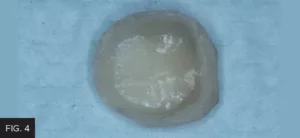

At this point, the temporary impression was set aside until the tooth was re-prepared for the new restoration. Once the temporary crown was fabricated using Inspire Esthetic Provisional Composite (Clinician’s Choice), it was necessary to quickly recontour and establish proper occlusion as well as remove some flash that resulted from the perforated impression. This was easily accomplished with finishing burs prior to cementation. (FIG. 4)

The temporary crown was removed from matrix and quickly recontoured to remove bulk and flash and then polished.